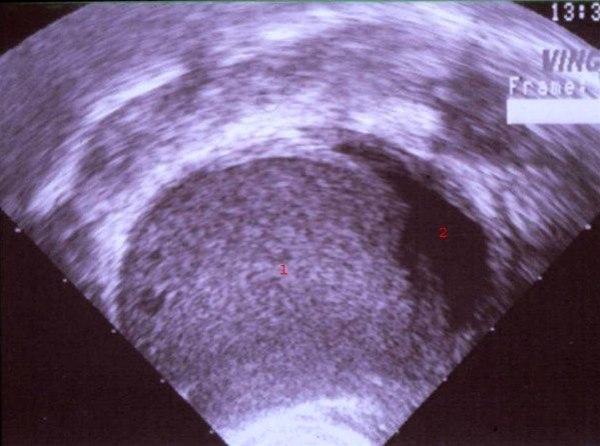

Endometriom

1. Endometrie-tumormasse

2. Uteruscavitet